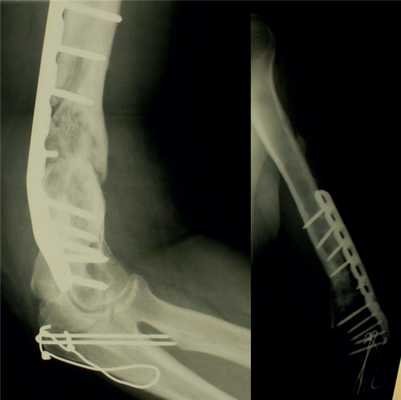

Диагноз: ложный сустав левой плечевой кости.

На рис. 10-14 Рис. 10. Рентгенограмма пациентки Н. до операции. Рис. 14. Внешний вид и функция пациентки Н. через 8 мес после операции. представлены этапы обследования и лечения пациентки Н.

Рис. 11. Пациентка Н. Оперативное лечение: резекция зоны ложного сустава левой плечевой кости, остеосинтез пластиной и винтами. Пластика свободным кровоснабжаемым трансплантатом из внутреннего мыщелка бедренной кости.

Рис. 12. Рентгенограммы пациентки Н. после операции.

Рис. 13. Рентгенограммы пациентки Н. через 8 мес после операции.